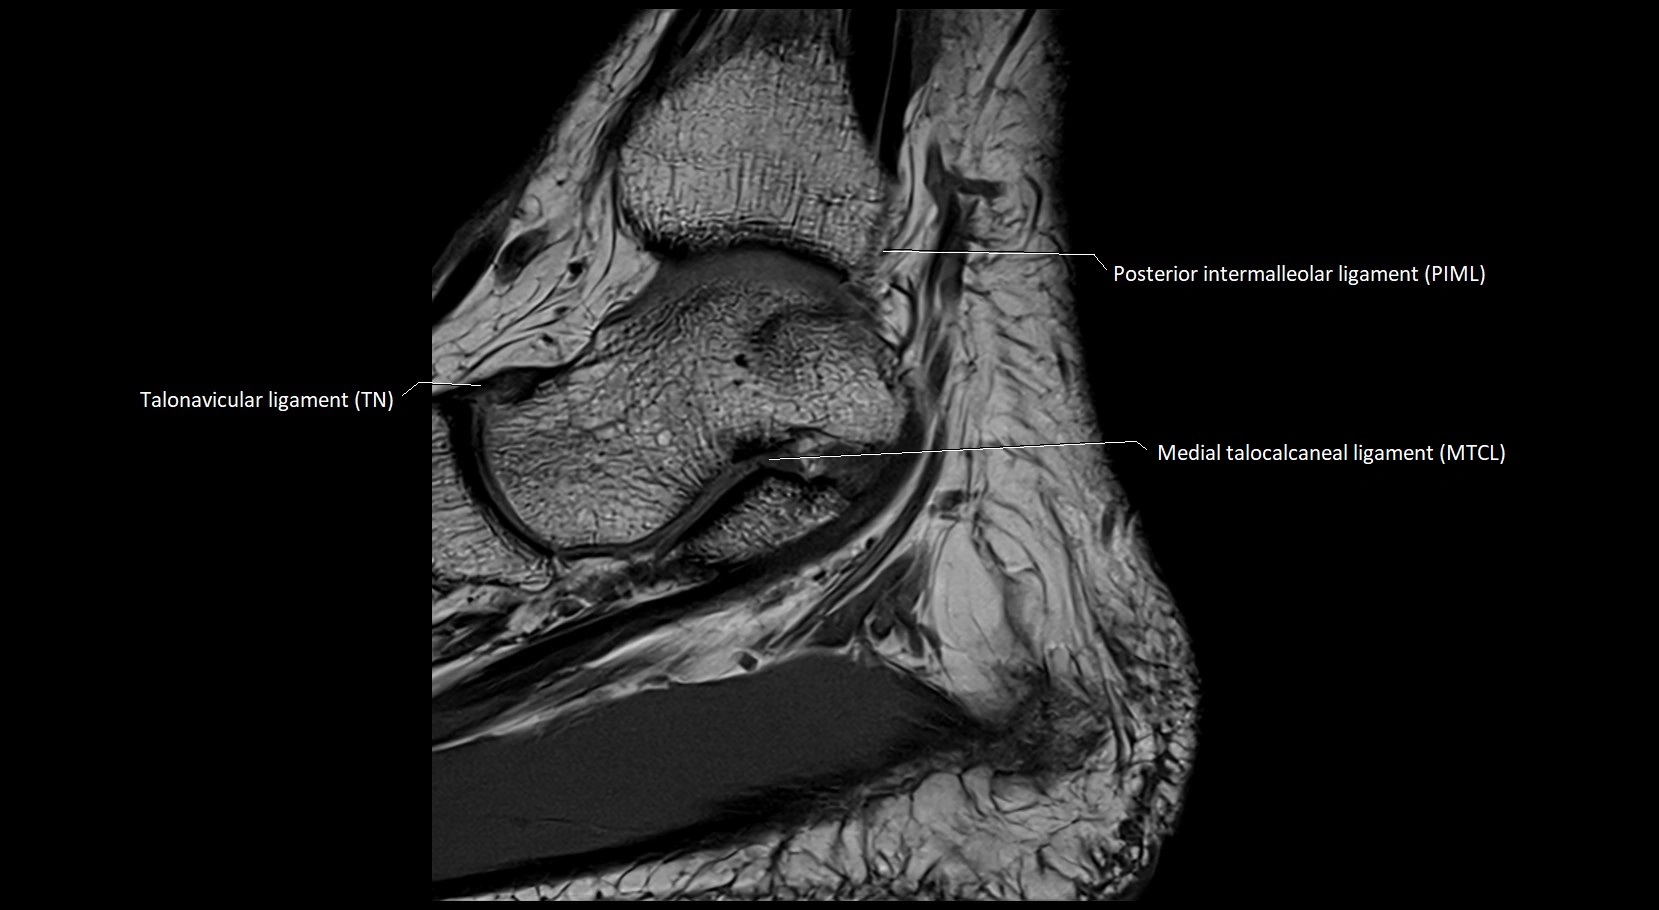

MRI image

image